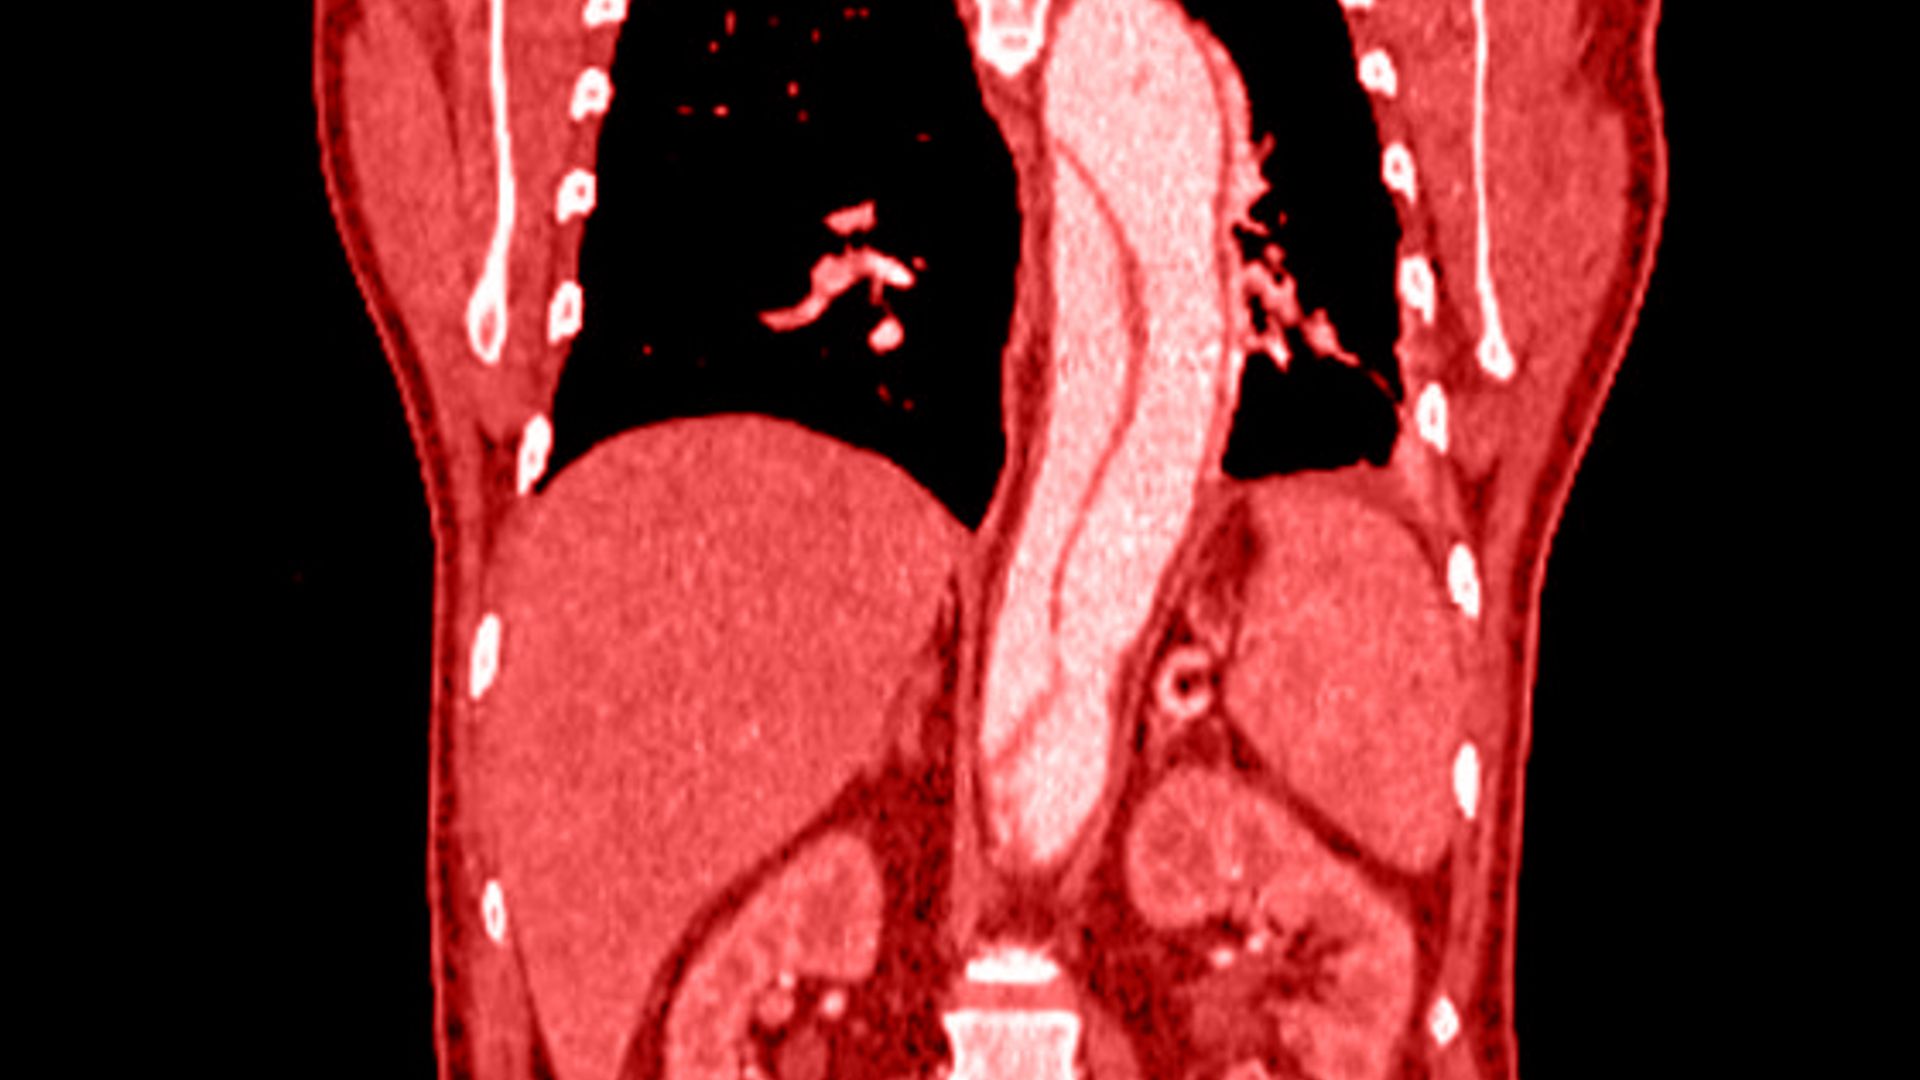

L’aorta è il vaso sanguigno principale del tuo corpo, essenziale per trasportare il sangue dal cuore verso il basso. A volte le pareti di questo tubo elastico si indeboliscono e si gonfiano progressivamente, richiedendo un’attenta valutazione clinica.

Molti pazienti convivono per anni con piccole anomalie vascolari senza alcuna necessità di un intervento chirurgico. Tuttavia, quando l’aneurisma all’aorta addominale raggiunge i 5 cm, il rischio di una pericolosa rottura aumenta e l’operazione diventa strettamente necessaria.

Generalmente, un aneurisma dell’aorta addominale inizia a essere considerato a rischio di rottura quando il suo diametro raggiunge i 5 cm. Superata questa soglia critica, lo specialista vascolare consiglierà di programmare un intervento per mettere in sicurezza il vaso.

La tecnica più avanzata è quella endovascolare (EVAR). Attraverso piccole punture all’inguine, il chirurgo inserisce una protesi navigando dall’interno delle arterie, andando a sigillare l’aneurisma senza dover ricorrere a grandi incisioni addominali.

Il metodo diagnostico principale e totalmente indolore è l’EcoColor Doppler dell’aorta addominale. Questo esame ecografico consente al chirurgo vascolare di misurare il diametro dell’arteria con precisione millimetrica in pochi minuti.